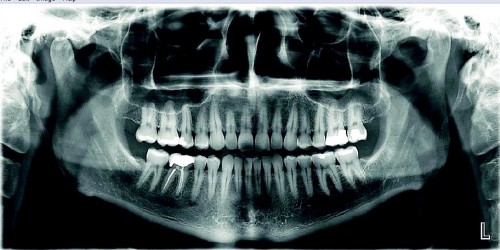

- 3D skenēšana un radiogrāfija nodrošina detalizētus attēlus par zobiem, žokļiem un apkārtējiem audiem.

- Datortomogrāfija (CT) sniedz trīsdimensiju attēlus, kas nepieciešami sarežģītām procedūrām, piemēram, implantācijai vai sakņu kanālu ārstēšanai.

Mūsu speciālisti izmanto progresīvas tehnoloģijas – trīsdimensiju skenēšanu, rentgenu, intraorālās kameras un datortomogrāfiju, lai precīzi identificētu visas mutes dobuma problēmas.